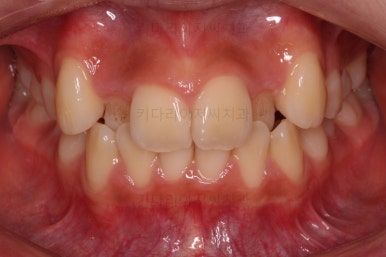

마찬가지로 초진 시 얼굴모습인데요.

덧니 때문에 활짝 웃지 못하고, 웃는 모습도 부자연스럽네요.

옆모습의 입술이 약간의 돌출된 느낌이 있지만 치아 자체가 나와서 생긴 돌출감이라기 보다 두툼한 입술에서 생긴 돌출감이라 이번 환자분은 비발치로 최대한 가지런하게 해보기로 했어요.